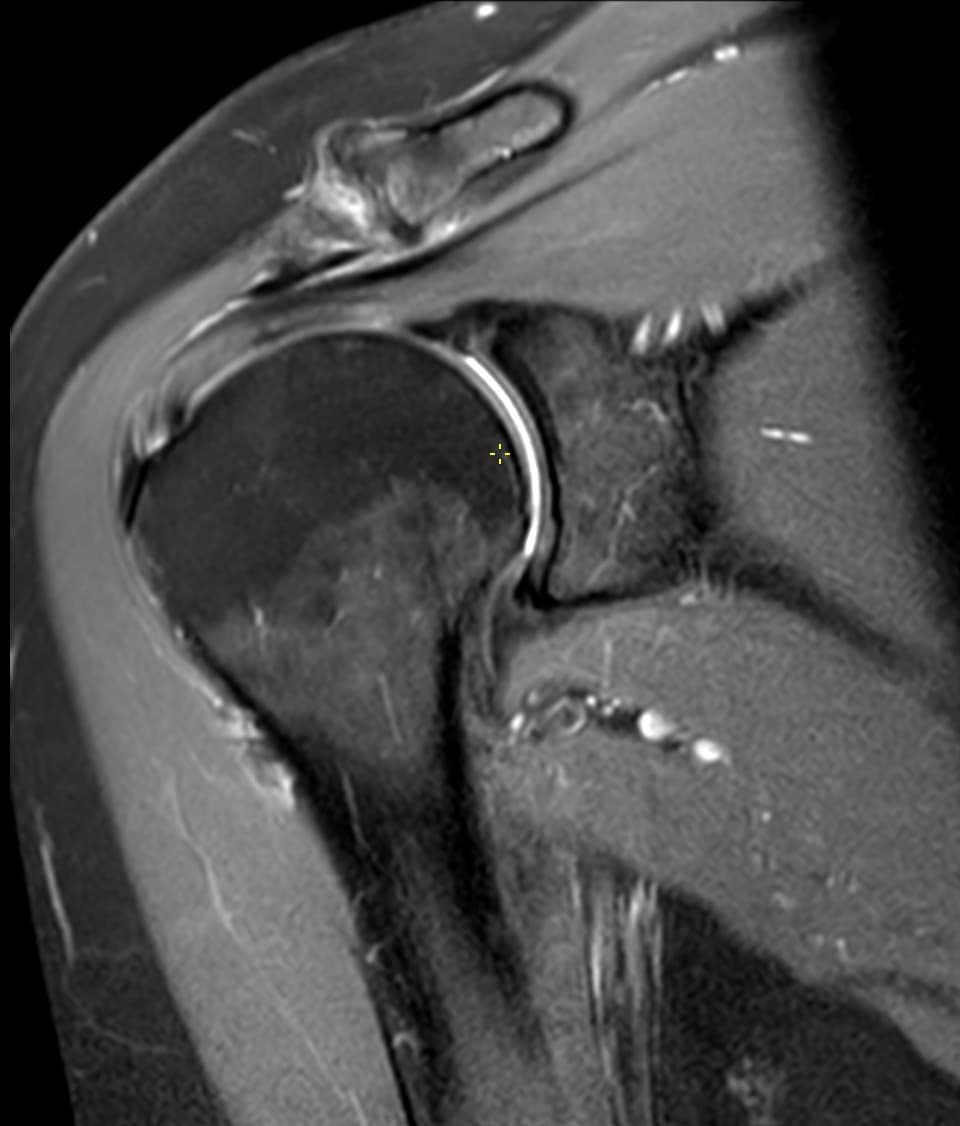

En second-opinion MRI-vurdering er mest værdifuld, når den første rapport ikke besvarer det kliniske spørgsmål tilstrækkeligt, eller når fund ikke passer med symptomer og klinisk undersøgelse.

Typiske henvisningssituationer er vedvarende smerter trods behandling, uoverensstemmelse mellem tidligere rapporter, uklare postoperative fund eller behandlingsvalg med høj konsekvens som kirurgi.